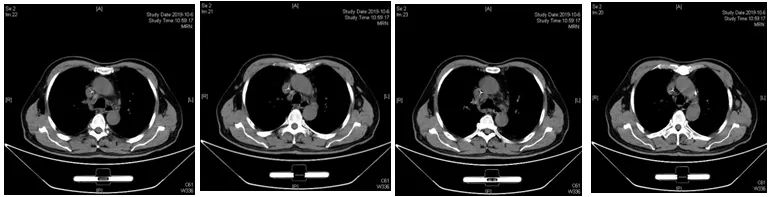

2019-12-28至2020-03-25:4周期R-CPER方案治疗(美罗华600mg静脉泵入+西达本胺片20mg biw+强的松100mg d1-5+依托泊苷100mg d1-5+来那度胺胶囊10mg d1-14)(21天一治疗周期)

4周期R-CPER后复查颈胸腹盆腔加强CT,双侧腋窝淋巴结较前消失、减少,纵膈淋巴结较前部分增大(组织病理学检查未发现恶性肿瘤细胞),疗效评估:PR,提示治疗有效。患者体能状况好转,有条件接受后续治疗。